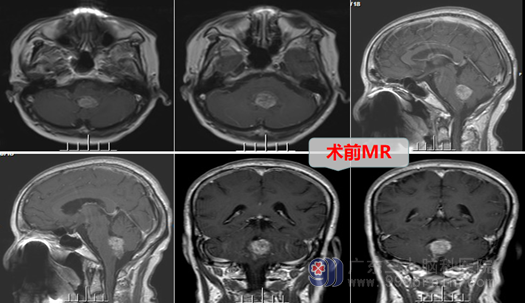

劳女士8年前无明显诱因出现阵发性的头晕,无明显恶心呕吐等不适,曾到当地医院就诊,查头部MR检查提示四脑室占位,当地做不了这种手术,于是开始了间断而漫长的“对症治疗”,每次一出现头晕不适的症状就去医院输液、吃药,稍有好转后就出院。如此反复多年,劳女士的头晕、头痛症状不见明显好转,近半年来劳女士甚至出现了行走不稳的症状。这让劳女士一家都很紧张,为进一步检查及治疗,劳女士终于在家人的劝说下来到三甲脑专科医院—广东三九脑科医院就诊,门诊拟“第四脑室占位”收住我科。

入院后,主管医生邓心情在对劳女士进行一系列相关检查,外十科在欧阳辉主任的带领下,对劳女士的病情仔细分析、讨论,认为劳女士的肿瘤大,主体位于第四脑室,与脑干关系密切,属于脑干-四脑室肿瘤,必须手术治疗,但由于肿瘤可能从脑干长出,手术风险很大。在完善相关术前准备,确认劳女士无手术禁忌症后,医生详细向其家属解释了病情,说明了手术的必要性和危险性。在征得患者及其家属的理解和同意后,外十科为其进行了“后颅窝开颅,脑干-第四脑室内占位切除术”,术中见肿瘤确实是从第四脑室底延髓背侧长出,肿瘤与脑干黏连,欧阳辉教授在显微镜放大下,剖开小脑下蚓部,沿肿瘤周边游离,精准、分块切除肿瘤,术中冰冻结果提示:低级别神经源性肿瘤(最后常规病理证实为室管膜瘤),医生如履薄冰、如临深渊,虎口拔牙,细心切除肿瘤大小约4*4*3cm,相邻脑干、血管解剖保护良好。手术顺利成功,现劳女士各方面恢复良好,无手术并发症发生。